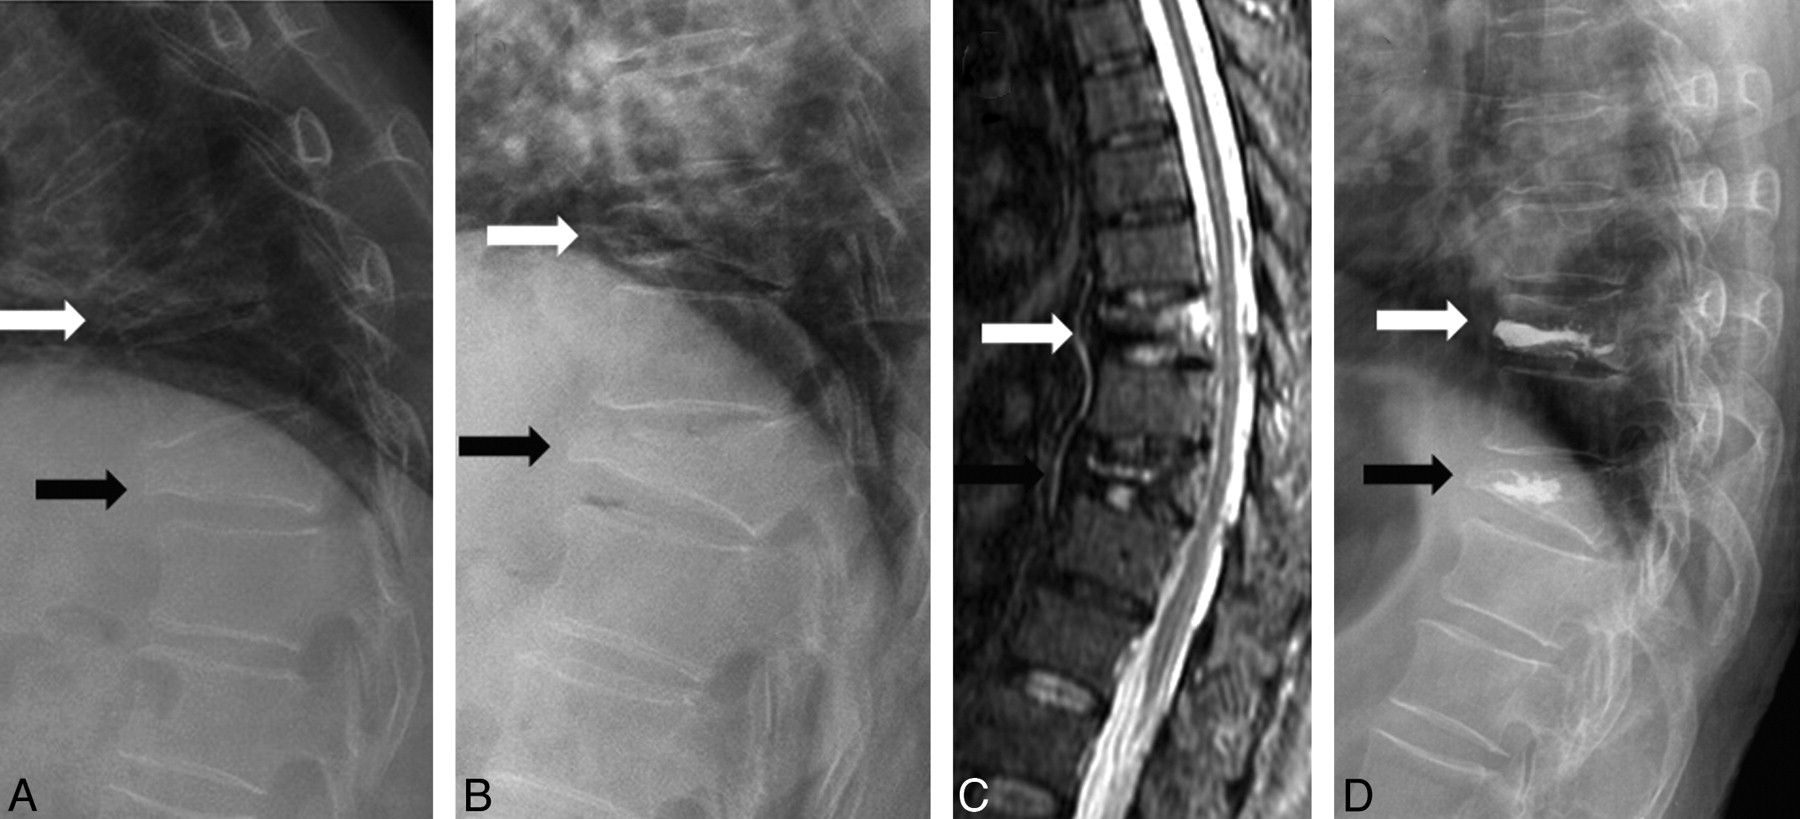

In this study, 87.5% of 144 MR imaging−proved edematous VCFs were demonstrated to be mobile. The sensitivity of dynamic radiographs in diagnosing the MR imaging−proved edematous VCFs is 0.87. However, in patients with painful VCFs that need vertebroplasty or surgical intervention, 99% of patients can be shown to have at least 1 mobile VCF. The sensitivity of dynamic radiographs in diagnosing the painful vertebrae in patients with severe pain is 0.99. An explanation is that not all edematous vertebrae are mobile; however, in patients with severe back pain who need vertebroplasty or surgical treatment, there is always at least 1 mobile vertebra. Toyone et al8 demonstrated a significant correlation between back pain and changes in the wedging rate from a supine to standing position. Changes in the wedging rate of >10% were always associated with more severe back pain. If the vertebrae are edematous but not mobile, the pain severity should be lower. So in a patient with mobile and nonmobile MR imaging−proved edematous VCFs, the mobile VCF should be the major pain source. In this study, 1 patient had 3-level compression fractures: 1 mobile and 2 nonmobile. We only treated 2 vertebrae (1 mobile and 1 nonmobile), and he still experienced dramatic pain improvement (Fig 3).

A 74-year-old man with severe back pain due to T6, T10, and L1 compression fractures. A and B, Sitting (A) and supine with bolster (B) lateral radiographs show mobility at L1 (black arrow) but no mobility at T6 (hollow arrow) and T10 (white arrow). C, Contrast-enhanced T1-weighted MR image demonstrates contrast enhancement at T6, T10, and L1. D, Postvertebroplasty lateral radiograph shows cement filling in T10 and L1. Vertebroplasty was not performed at T6, but the patient still showed dramatic improvement.

Because MR imaging can provide an accurate diagnosis, what is the role of dynamic radiographs? In the time that elapses between the initial MR imaging evaluation and vertebroplasty, it is possible for additional fractures to occur. Benz et al10 recommended a repeat preprocedural MR imaging obtained within 1 week in select candidates to help ensure that all painful fractures are treated. However, the disadvantages of preprocedural MR imaging include the time, expense, and demands on the radiology department. Because dynamic radiographs are sensitive in diagnosing the painful vertebrae, they can be used as a preprocedural re-evaluation examination to rule out any new lesions if MR imaging was not recently performed. The dynamic radiographs will be more valuable in patients who cannot undergo MR imaging. In addition to its diagnostic value, dynamic radiographs can help interventionalists estimate the postprocedural vertebral height and shape and cement injection area and amount. It can also help interventionalists assess the feasibility of vertebroplasty in the vertebral plana (Fig 1, black arrow).